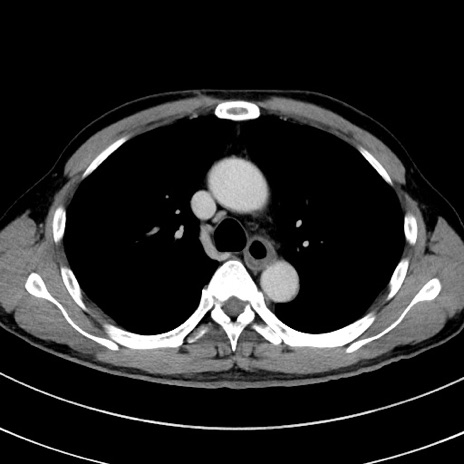

症例8(横断像)

【症例】 60歳代男性

【主訴】 黒色吐物

【現病歴】 4日前から嘔気自覚、2日前の朝食後にも嘔気あり、自分で手で嘔吐反射起こし嘔吐したところ血が混ざっていたため受診。

【既往歴】 5年前汎発性腹膜炎を伴う急性虫垂炎で手術、高血圧、前立腺肥大症、高脂血症

【身体所見】 腹部正中に手術癩痕あり 腹部平坦・軟圧痛なし膨満感あり

【データ】WBC 8400、CRP 4.54